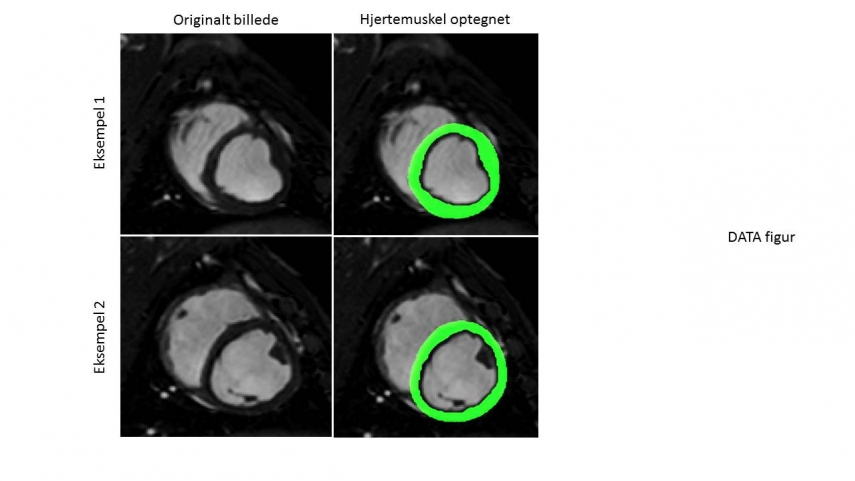

- Træning af kunstig intelligens til genkendelse af hjertemuskulaturen

- Volumenberegninger af hjertemuskulaturen baseret på resultater